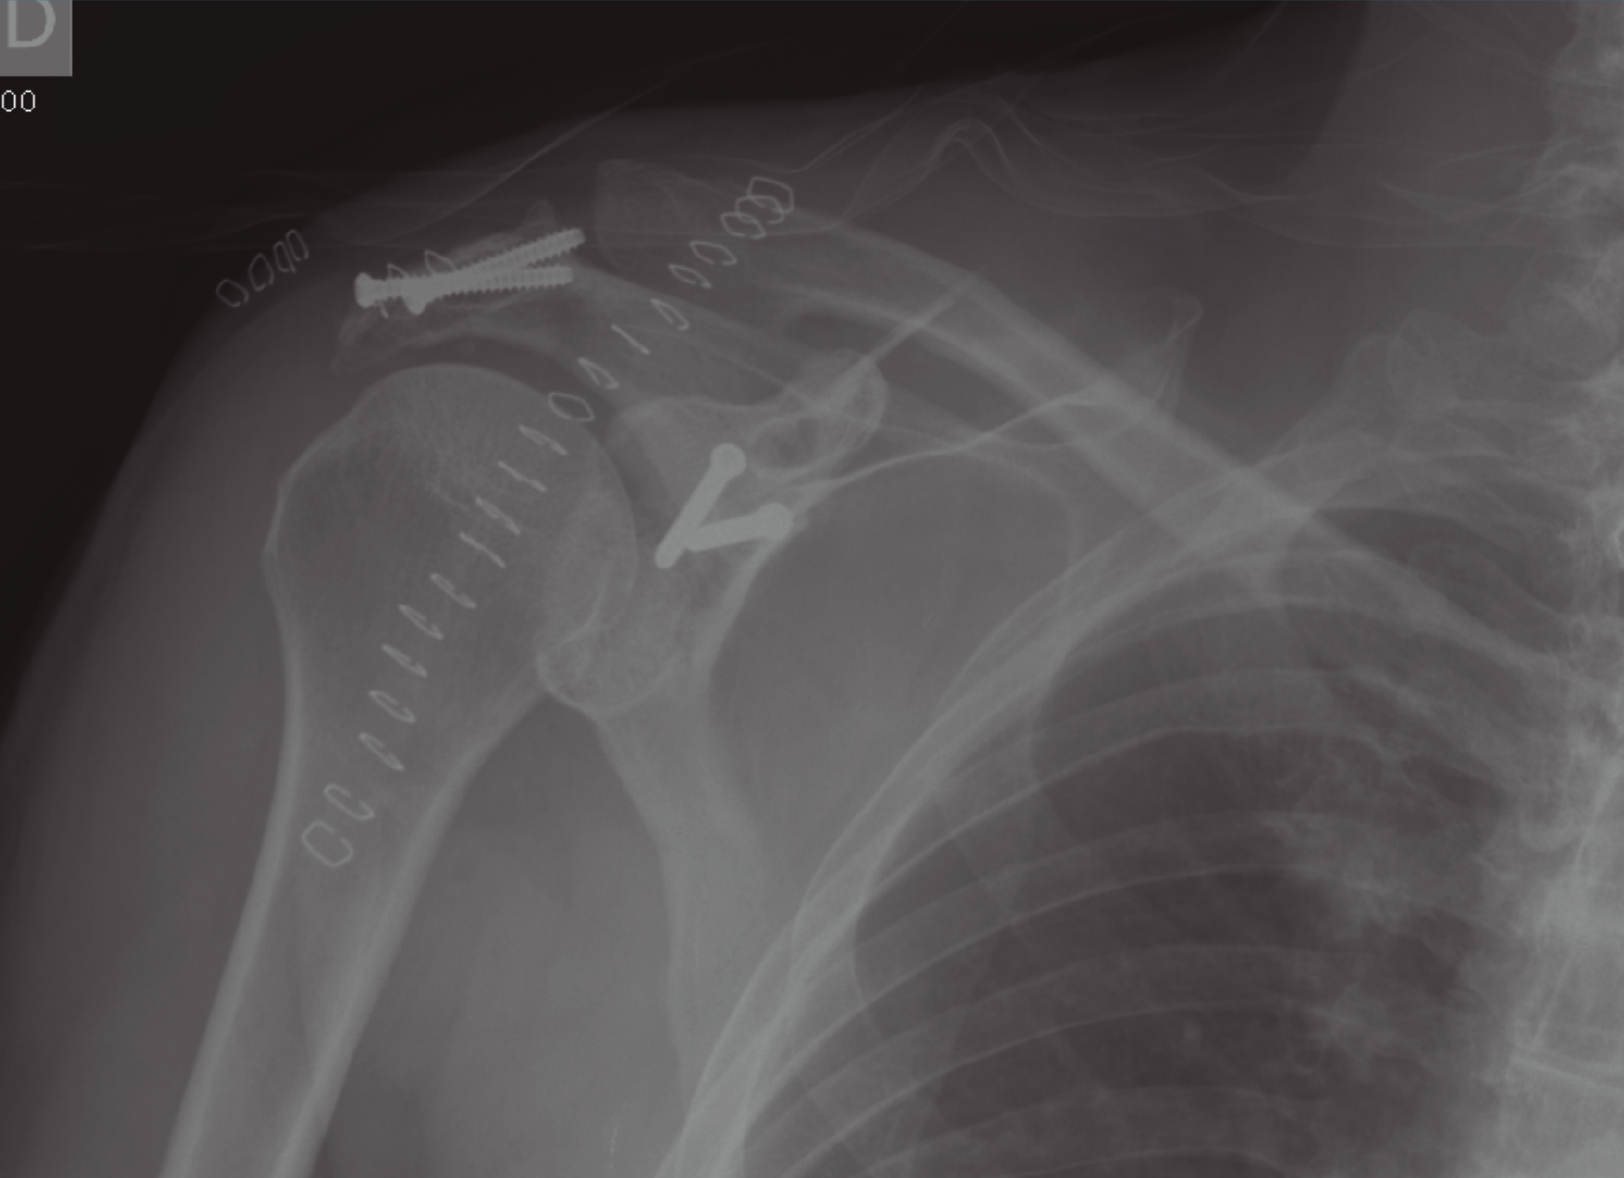

El complejo suspensorio superior del hombro es un anillo óseo y de tejidos blandos formado por el rodete glenoideo, la coracoides, el ligamento coracoclavicular, la porción distal de la clavícula, la articulación acromioclavicular, el ligamento coracoacromial y el acromion. La lesión de dicho anillo a 2 niveles supone una alteración biomecánica importante, que requiere tratamiento quirúrgico dado el potencial de inestabilidad que supone la disrupción del complejo suspensorio del hombro. Presentamos el caso de un paciente que sufrió fractura del acromion y de la cavidad glenoidea con desplazamiento significativo. Tras la estabilización del paciente se procedió a la osteosíntesis de la glena y el acromion con tornillos mediante un abordaje deltopectoral.

The superior shoulder suspensory complex is a bone and soft tissue ring formed by the glenoid cavity, the coracoid, the coracoclavicular ligament, the distal portion of the clavicle, the acromioclavicular joint, the coracoacromial ligament and acromion. The lesion of the ring at 2 levels implies an important biomechanical alteration, which requires surgical treatment because of the potential for instability that involves the disruption of the superior shoulder suspensory complex. We present the case of a patient who suffered a fracture of acromion and glenoid cavity with significant displacement. After stabilization of the patient, osteosynthesis of the glena and acromion with screws was performed using a deltopectoral approach.